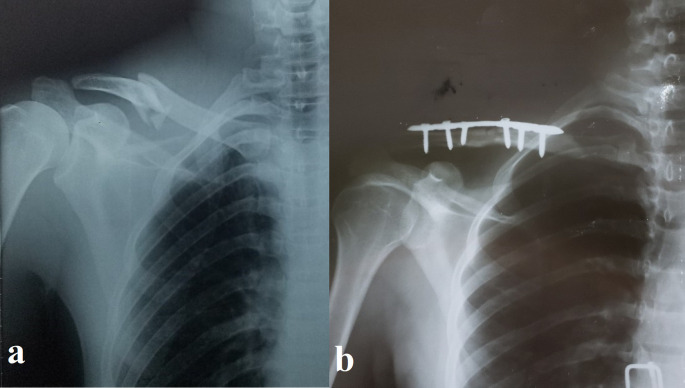

Background: This study assessed the functional outcomes and complications of open reduction and internal fixation (ORIF) using precontoured superior clavicle locking plates for displaced midshaft clavicular fractures.

Methods: In a prospective two-center study at Al-Thawra Modern General Hospital and Kuwait University Hospital, Sana'a, Yemen, from January 2018 to September 2024, 65 patients (≥18 years) with closed, displaced midshaft clavicular fractures (displacement >2 cm, shortening >2 cm, comminution, or skin tenting) underwent ORIF. Functional outcomes were evaluated six months postoperatively using the University of California, Los Angeles (UCLA) shoulder rating score. Data were analyzed using SPSS version 26.

Results: The mean patient age was 32.09 years (83.1% male, n=54). Road traffic accidents were the primary mechanism of injury (66.2%, n=43). At 6 months, the mean UCLA score was 32.46 ± 2.54, with 98.5% (n=64) achieving good or excellent outcomes (UCLA score ≥27) and 1.5% (n=1) fair/poor. Complications included hardware irritation (1.5%, n=1), hardware failure (3.1%, n=2), and superficial infections (1.5%, n=1). All patients (100%) reported satisfaction with their outcomes. The UCLA scores varied significantly according to injury mechanism, side, and age, with older patients showing lower scores.

Conclusion: ORIF with precontoured locked plates yielded promising functional outcomes, high patient satisfaction, and low complication rates. However, the observational design, lack of a control group, and 6-month follow-up limit broader conclusions. Larger controlled studies are needed to validate these findings and guide the optimal management of displaced midshaft clavicular fractures.